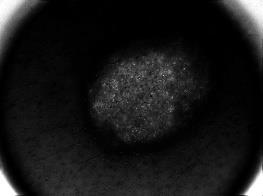

Skin lesion segmentation is one of the crucial steps for an efficient non-invasive computer-aided early diagnosis of melanoma. This paper investigates how color information, besides saliency, can be used to determine the pigmented lesion region automatically. Unlike most existing segmentation methods using only the saliency in order to discriminate against the skin lesion from the surrounding regions, we propose a novel method employing a binarization process coupled with new perceptual criteria, inspired by the human visual perception, related to the properties of saliency and color of the input image data distribution. As a means of refining the accuracy of the proposed method, the segmentation step is preceded by a pre-processing aimed at reducing the computation burden, removing artifacts, and improving contrast. We have assessed the method on two public databases, including 1497 dermoscopic images. We have also compared its performance with classical and recent saliency-based methods designed explicitly for dermoscopic images. The qualitative and quantitative evaluation indicates that the proposed method is promising since it produces an accurate skin lesion segmentation and performs satisfactorily compared to other existing saliency-based segmentation methods.